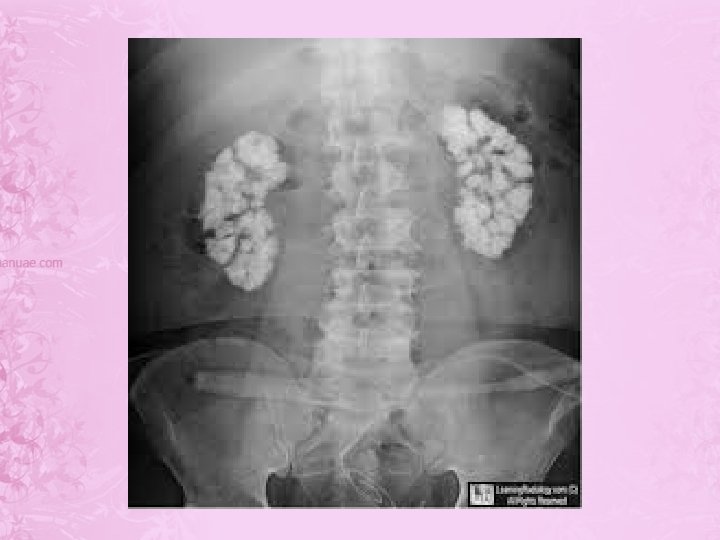

investigation • serum calcium upper limit (10. 9 mg/dl) • • serum phosphate lower limit (3 mg/dl) excretion of ca in urine. serum alkaline phosphatase. serum PTH.